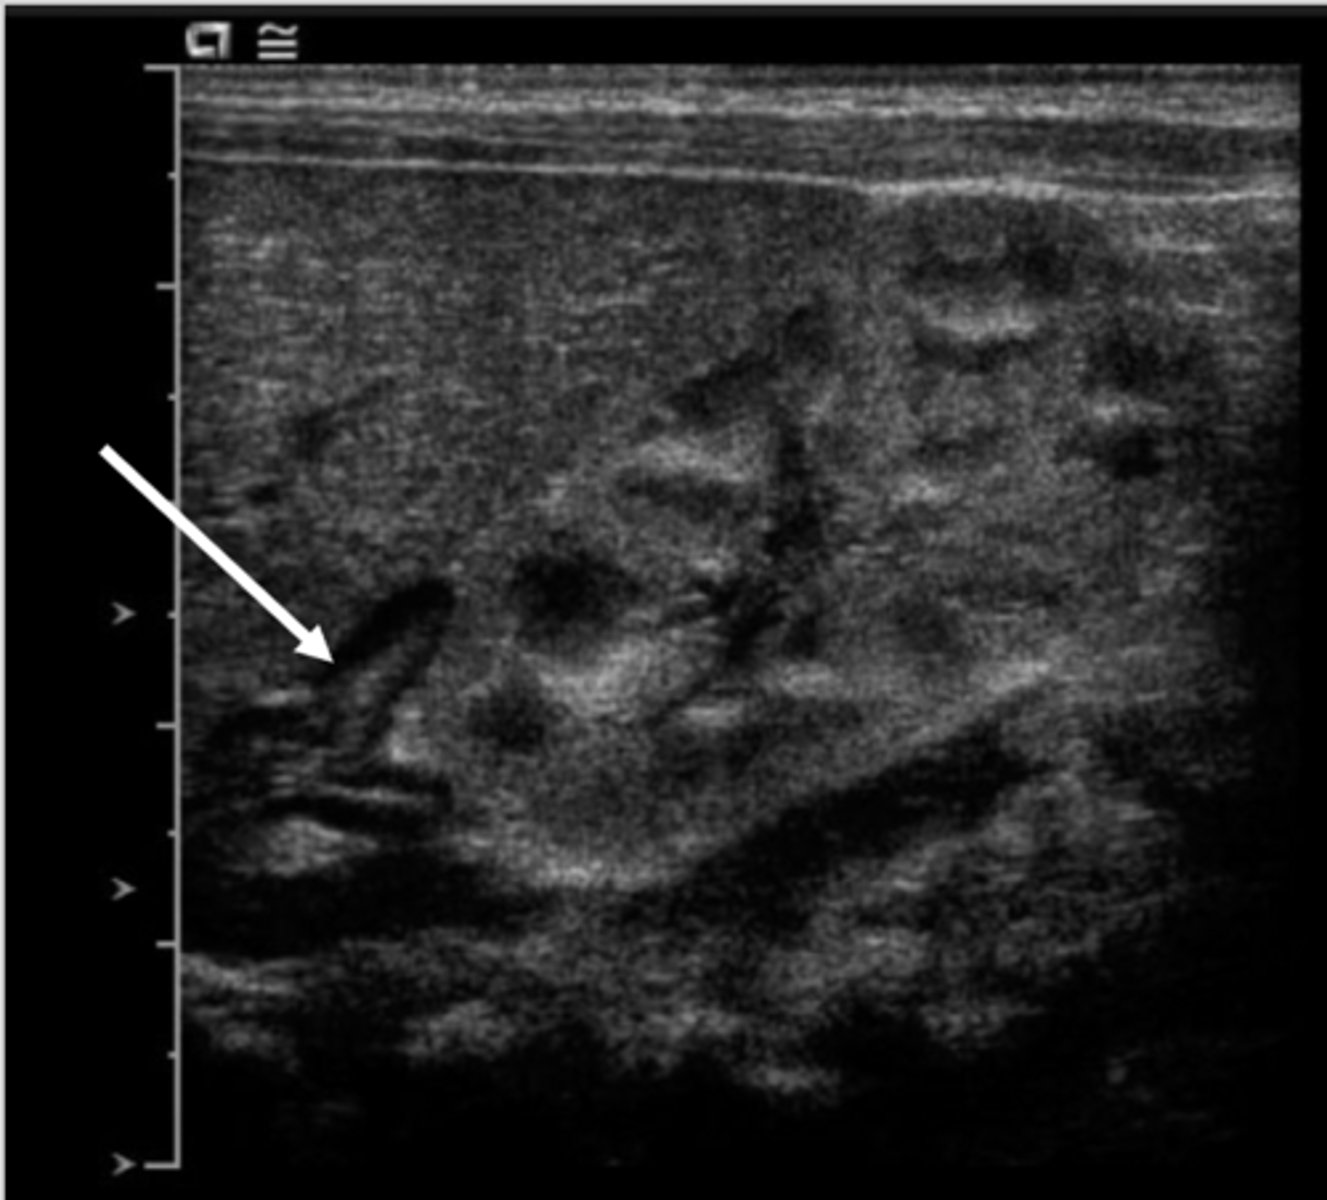

What is the typical sonographic appearance of a neuroblastoma?

Heterogeneous, hyperechoic mass with poorly defined margins

What will Color Doppler demonstrate on a neuroblastoma?

Capsular flow

What will Spectral Doppler demonstrate on a neuroblastoma?

Low-resistance arterial waveforms